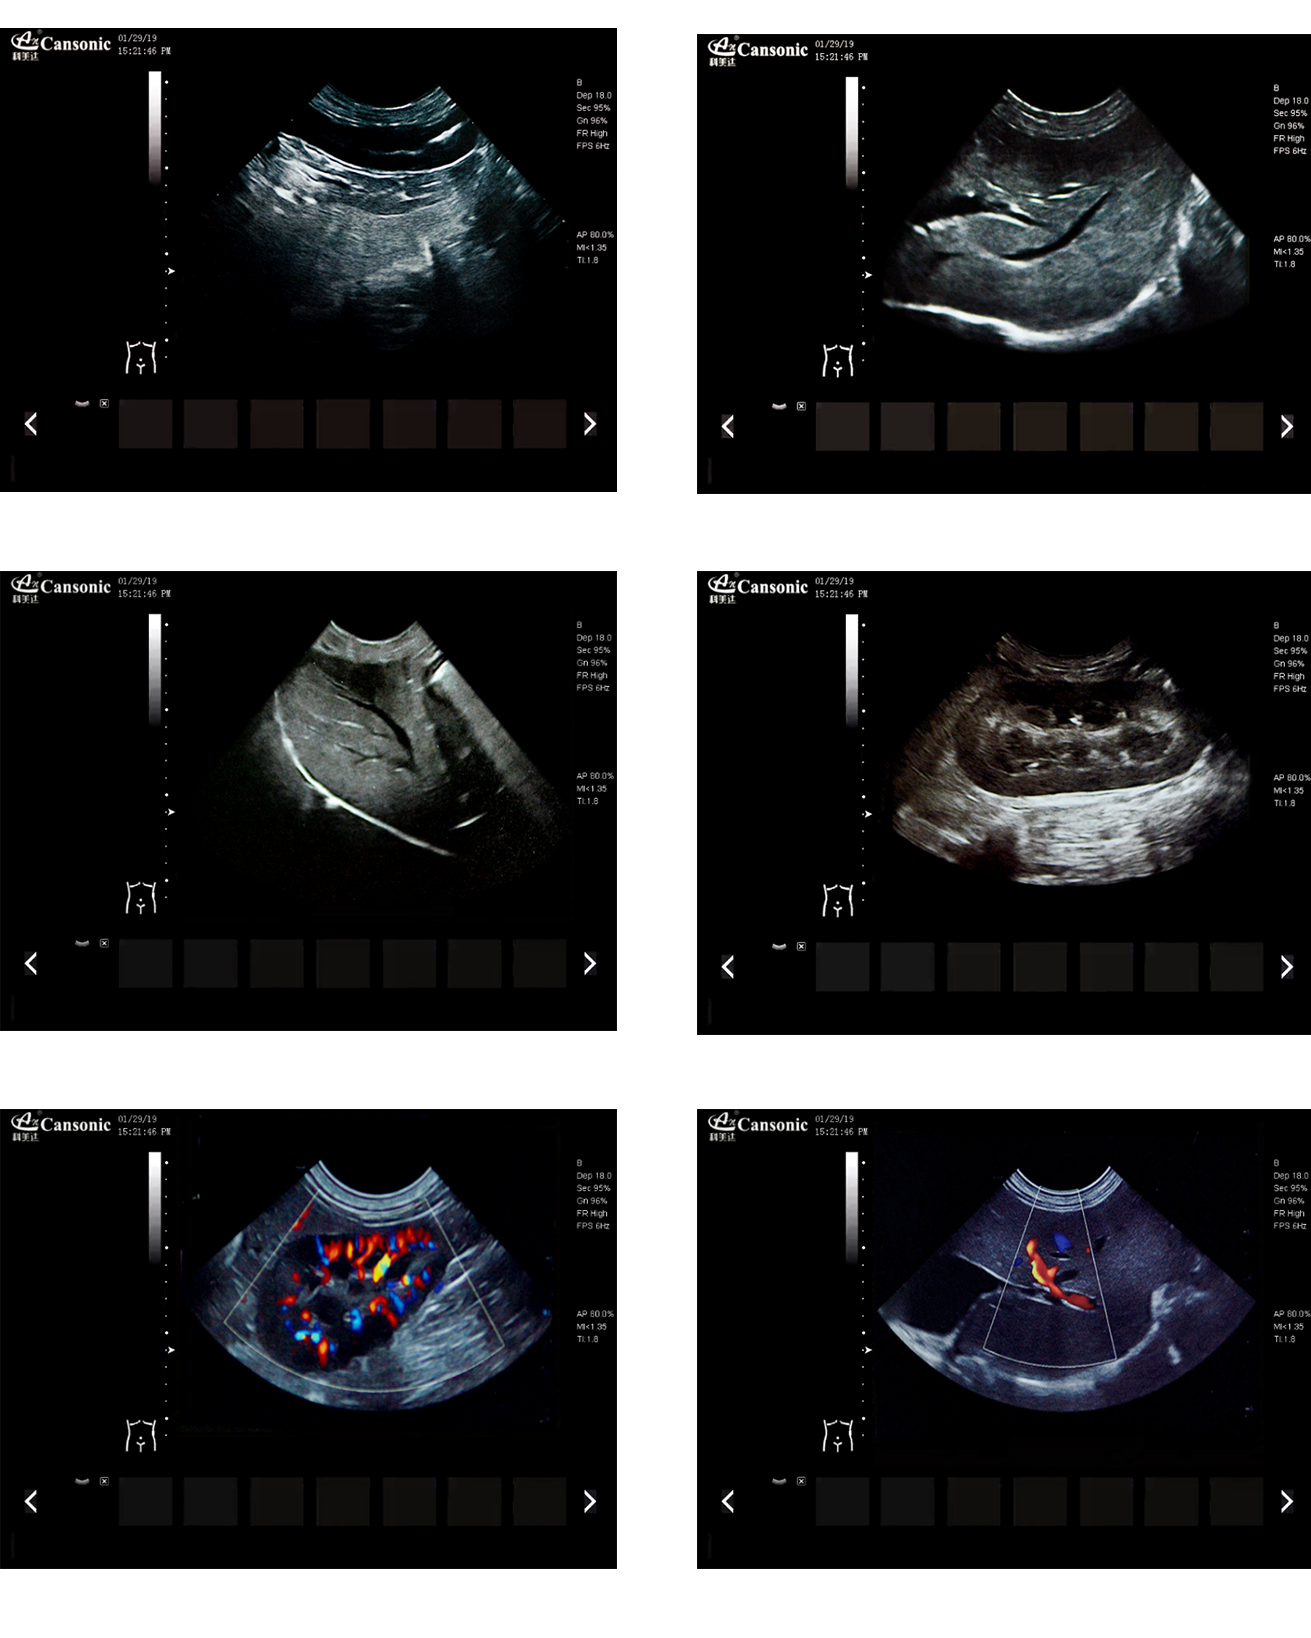

臨床圖示

產品特點:

1、薈萃前沿成像技術,實現高精與靈便的完美融合,提供完整的動物彩超診療方案

2、專業的獸用測量軟件,簡捷的工作流,適合犬、貓、馬、牛、羊等 各類大小動物

3、iClear斑點噪聲抑制抑制噪聲干擾,使動物組織結構更清晰

4、具有廣泛的動態范圍,顯示出色的組織均勻性,減少了偽影及噪聲

5、精細血流識別技術,增加了可疑病變更多的信息分析

6、先進的算法帶來清晰的穿刺針顯示,降低穿刺活檢操作難度

7、圖像優異,同時性能穩定,每天能進行大量的動物超聲檢查